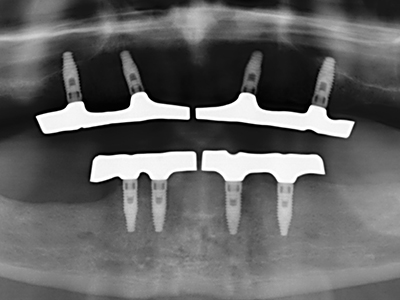

Il tessuto osseo non è semplicemente una struttura minerale, ma contiene anche una percentuale significativa di fibre di collagene. Ciò significa che non possiede solo una buona forza di compressione, ma anche un certo livello di flessibilità che è possibile sfruttare durante l'esecuzione degli accrescimenti di osso. Nella procedura di espansione classica con incisione ossea, la cresta alveolare atrofizzata viene incisa longitudinalmente ed espansa con cautela dopo aver raggiunto una profondità di osteotomia adeguata (figg. 13-16), idealmente senza una sostanziale rimozione del periostio (Brugnami, Caiazzo et al. 2014, Stricker, Fleiner et al. 2014). I sistemi a piastra e vite con distanza di espansione incrementale si sono dimostrati efficaci nella separazione delle due lamelle ossee restando al di sotto della soglia di frattura. In generale, sono richieste larghezze dell'osso residuo di almeno 3-4 mm (Chiapasco, Zaniboni et al. 2006) per garantire un'adeguata flessibilità e una copertura sufficiente dell'osso per gli impianti futuri. Se necessario, un'osteotomia di rilascio verticale su uno o più lati può migliorare la flessibilità. Una combinazione con ulteriori tecniche di accrescimento, in particolare dal lato buccale, è stata descritta come un'alternativa alla tecnica classica.

La procedura di incisione è particolarmente atraumatica e non comporta una perdita significativa di dimensione durante l'utilizzo delle seghe piezoelettriche, così come non si notano differenze rilevanti tra impianti in mandibole incise e impianti in una cresta alveolare senza deficit osseo (Chiapasco, Zaniboni et al. 2006, Danza, Guidi et al. 2009). Una sufficiente irrigazione continua è essenziale, tuttavia, in particolare con incisione profonda e localmente ristretta, per prevenire la sollecitazione termica nelle regioni apicali dell'osteotomia.